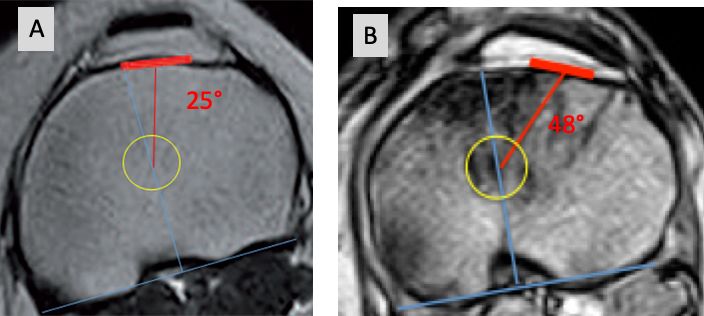

For many decades standardized 3° ER were used to bring the femur component parallel to the TEA by referencing to the posterior condylar axis. The new 3-D mega data clearly demonstrated that in knees planned for TKA surgery a wide range of internal rotation (minus 3 ER to 11° IR) of the posterior condylar axis to the TEA exists (Fig 10) [27,31,32].

For valgus knees it was well known that due to the possible hypoplastic lateral condyle the posterior condylar axis might be more than 3° of IR and many surgeons routinely used 5° ER to the TEA in valgus knees. A wide range from 3° to 12° of IR of the posterior condylar axis to the TEA could be shown with the new 3-D mega data for valgus knees also [32]. For varus knees it was long assumed that 3° of ER will fit for rotational alignment. Now we know that even in varus knees axial plane femur deformities are possible and show a wide range from 3° of ER (worn out posterior medial condyle) to 9° of IR (hyperplastic medial condyle) from the posterior condylar axis to the TEA (Fig 11) [32]. 32 % of femur needs more than 3-5° ER (6-11), whereas 10 % less than 3° ER (IR 3 to ER 2°) [31].

On average this angle is 25° with a wide range from 4 to 50°. 49% of knees show outliers > 5° and 15% more than 10°. Roughly 5° is equal to 1 mm, which correlates to the 5 mm of the TT-TG distance. Axial tibia component IR malalignment of more than 5° to the TT is clinically relevant [3].